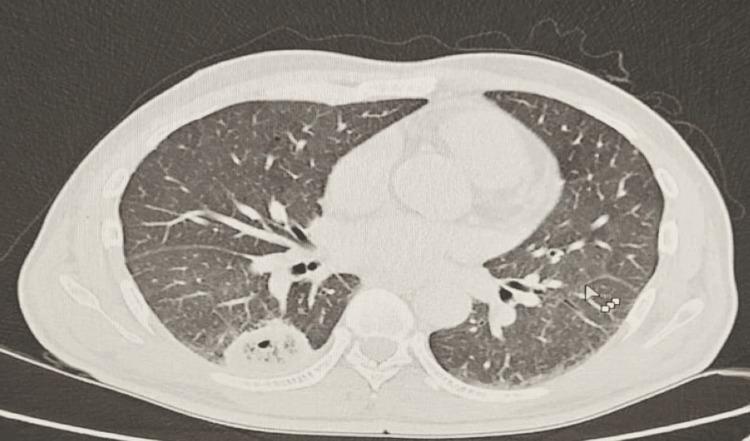

We report a rare case of a 59-year-old male patient with poorly controlled diabetes mellitus who presented with concurrent hepatic and pulmonary abscesses. Imaging revealed a large septated hepatic lesion and multiple bilateral pulmonary cavities. Cultures from blood and drained hepatic pus confirmed . Despite the lack of genomic testing, the clinical course was consistent with invasive syndrome (IKPS). The patient was treated successfully with prolonged intravenous and oral amoxicillin-clavulanate over six months, along with percutaneous drainage of the hepatic abscess. Follow-up imaging demonstrated near-complete resolution of both liver and lung lesions. This case highlights the importance of early source control and extended culture-guided antibiotic therapy in managing severe invasive infections in immunocompromised patients.

我们报告了一例罕见病例,一名59岁男性糖尿病患者,血糖控制不佳,同时出现肝脓肿和肺脓肿。影像学检查显示肝脏有一个大的分隔性病变以及双侧多个肺空洞。血液和引流的肝脓液培养结果证实了……。尽管缺乏基因组检测,但临床过程符合侵袭性……综合征(IKPS)。患者接受了为期六个月的延长静脉和口服阿莫西林 - 克拉维酸治疗,并对肝脓肿进行了经皮引流,治疗成功。随访影像学检查显示肝脏和肺部病变几乎完全消退。该病例强调了在免疫功能低下患者中,早期源头控制和延长的培养指导抗生素治疗在管理严重侵袭性……感染中的重要性。